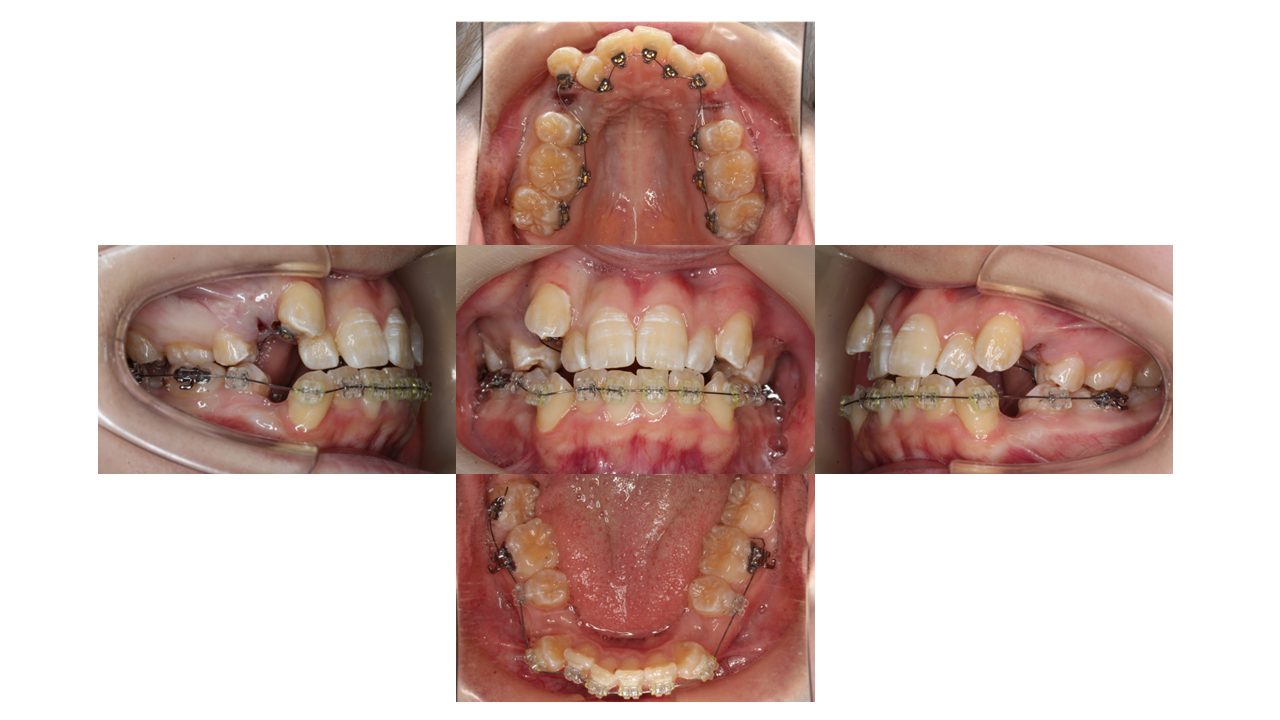

装置装着時の口腔内の状態です。

上下左右ともに4番目の箇所を抜歯し、ハーフリンガル(上:裏側/下:表側)の装置で動かしていきます。